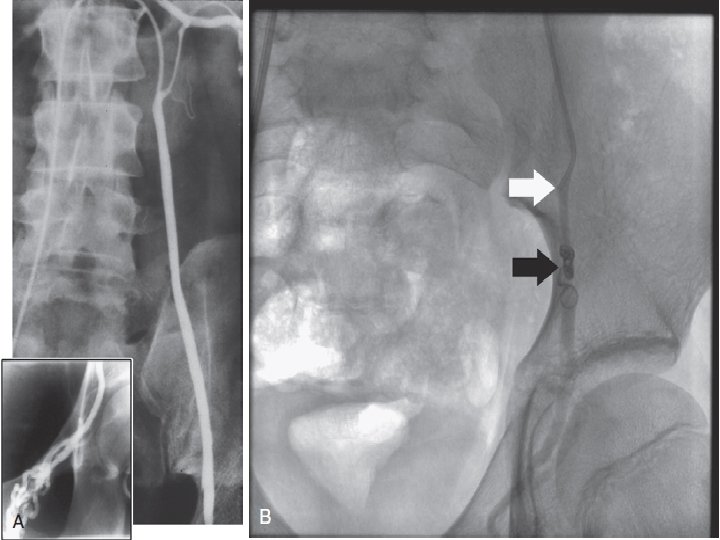

Venography of the internal spermatic veins has been used to diagnose and treat varicoceles. nearly 100% (Most Sensitive) of clinical varicocele patients will demonstrate reflux on venographic examination. left internal spermatic vein reflux has been reported in up to 70% of patients without a palpable varicocele. (High false positive results & Limited Specificity)

Radiographic Occlusion Techniques Does not prevent recurrence (4% to 11%) but allows visualization of all collaterals difficult to be seen with the 2 D view. Drawbacks: 1) Take 1 -3 hours to perform compared with 25 to 45 minutes required for surgical repair. 2) Femoral vein perforation or thrombosis. 3) Anaphylaxis to radiographic medium. 4) Recurrence with large varicoceles & with Failure to cannulate small collaterals. 5) Migration of the balloon or coil into the renal vein, resulting in loss of a kidney, pulmonary embolization.